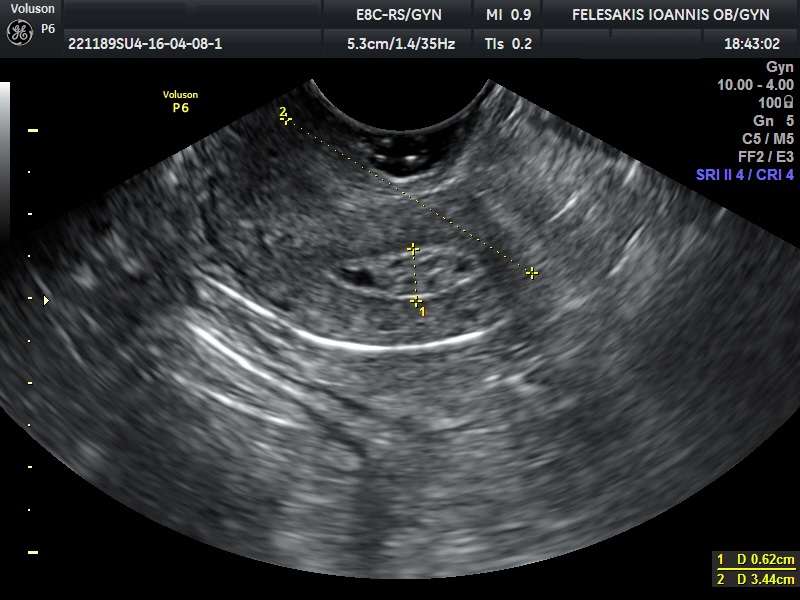

√ Κυστικά μορφώματα ωοθηκών

√ Πολυκυστικές ωοθήκες